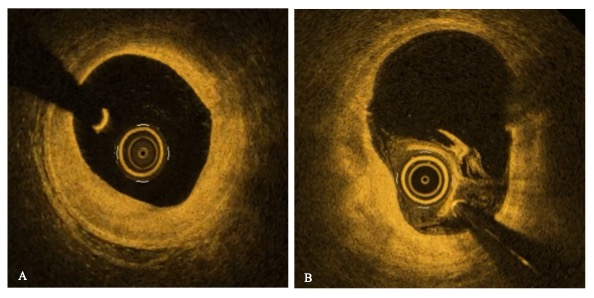

Background: Cardiac allograft vasculopathy(CAV) is the most common form of late rejection after heart transplantation.Early detection and monitoring of CAV are crucial for improving long-term outcomes.Aim of this work is to investigate pros/cons of each imaging modality and the potential of selected non-invasive biomarkers in predicting the presence and severity of CAV. Methods: We retrospectively analyzed clinical reports and angiographies of 63 living patients transplanted in Ospedale Monaldi. Levels of NT-proBNP, creatinine, LDL,Lp(a),IL-2R, IL-6, C-Reactive protein were statistically analyzed. Results: sample was stratified as follows:56% CAV0, 9% CAV1, 11% CAV2 and 24% CAV3 disease. IVUS(n=29)resulted positive in 67% cases of CAV0group, identifying a pre-clinical stage of disease.OCT(n=2)resulted positive in both patients, showing in one case a fibrotic infiltration of the vessel wall, diffusely involving the entire analyzed segment(Figure1A), and in the second case lipid accumulation at multiple sites along the vessel(Figure1B). Results about biomarkers are summarized in Figure2.CRP,NT-proBNP, and serum creatinine were significantly correlated with angiographically confirmed CAV(Figure3),whereas IL-2R and IL-6 showed a trend toward higher values in the CAV group. No statistically significant difference was found in mean LDLand Lp(a) levels between CAV0 and CAV-positive patients.No difference was found for all the aforementioned parameters between IVUS-pos and IVUS-neg patients. Discussion :the main findings of our study are the following:1)Intravascular imaging currently remains the sole system for preclinical diagnosis of the disease;while IVUS discriminates the presence of disease, OCT can reveal different disease phenotypes;2)CRP showed a statistically significant correlation with disease presence,while IL-2R and IL-6 exhibited an increasing trend with disease severity, confirming the role of inflammation in the development of CAV;3)no statistically significant differences were found for LDL or Lp(a) levels between groups, which underscores that CAV is not purely an atherosclerotic process;4)higher creatinine and NT-proBNP levels may reflect allograft dysfunction or ongoing vascular pathology in CAV patients. Conclusions :This study highlights the potential clinical value of inflammation, renal dysfunction and myocardial stress biomarkers in CAV patients, and advocate for an expanded use of intravascular imaging, especially OCT, for early CAV detection.